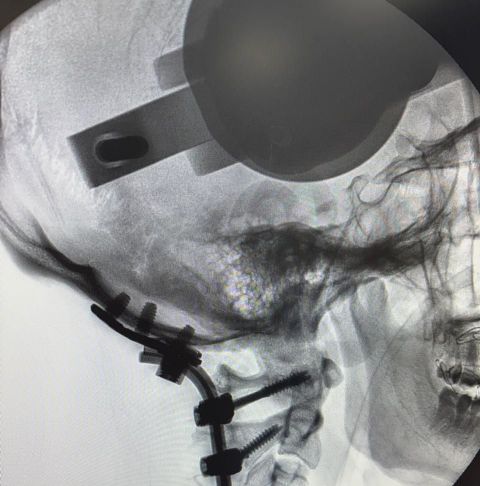

وفور وصول المريض، باشر فريق جراحة العمود الفقري التدخل بشكل عاجل، حيث أُجريت عملية جراحية معقدة ودقيقة شملت:

* إعادة المحاذاة بين الرأس والرقبة

* تثبيت الوصلة القحفية العنقية باستخدام تقنيات جراحية متقدمة

وقد تكللت العملية – ولله الحمد – بالنجاح، مما أسهم في استقرار الحالة وإنقاذ المريض من مضاعفات خطيرة كانت وشيكة.

قاد الفريق الجراحي الدكتور هاني نوران الحربي، بمشاركة نخبة من استشاريي جراحة العمود الفقري، في تجسيد واضح لما تمتلكه المدينة من كفاءات وطنية عالية وخبرات متقدمة في التعامل مع أدق وأندر الحالات الطبية.